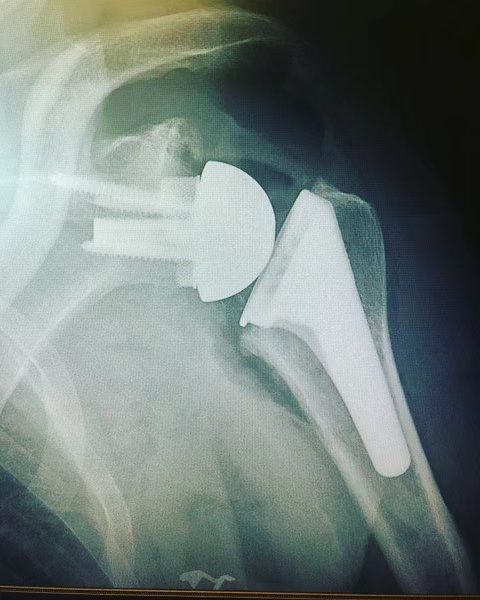

Dans les forme évoluées, ou en cas d'échec du traitement médical, une prothèse totale d'épaule inversée est proposée.

L'intervention consiste a remplacer les surface articuliraire abimer tout en restaurant les mobilités et l'indolence de l'épaule.

La coiffe des rotateurs étant détériorés, l'action du muscle deltoïde est privilégier pour animer l'épaule. Pour ce faire: les surface articulaire sont inversées:

une sphère est placée sur l'omoplate ( 4)

une cupule est placée au sommet de l'humérus ( 5).

Prothèse Totale d'Epaule Inversée